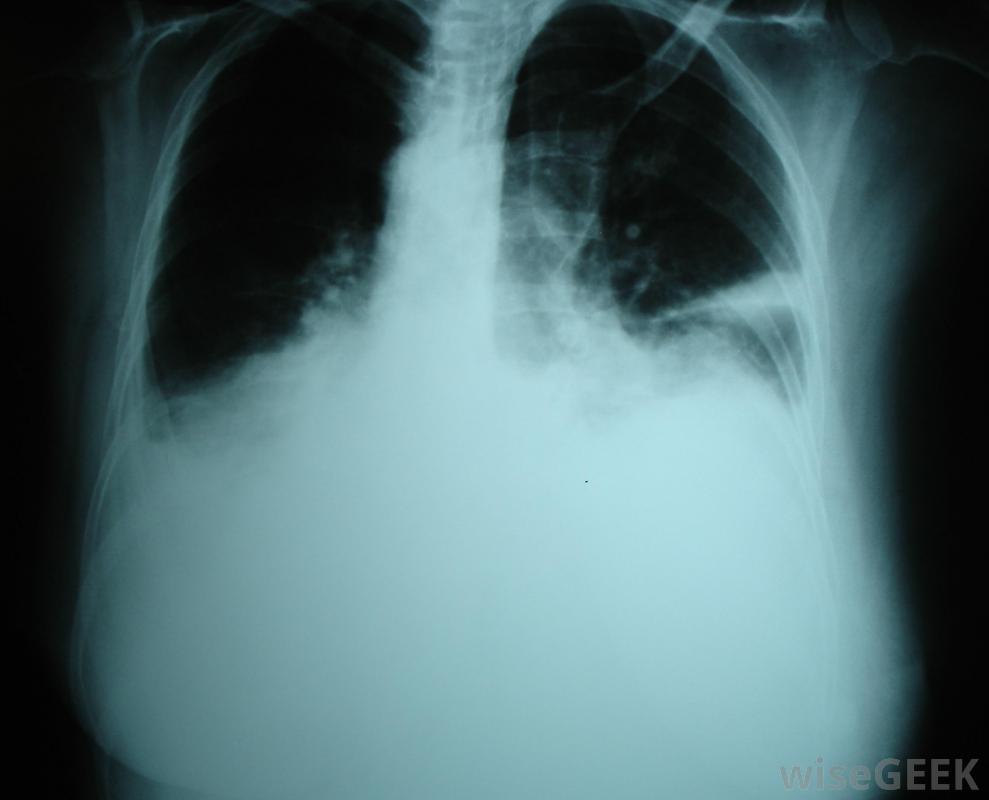

滲出性胸腔積液是一種富含蛋白質的液體在肺部周圍的腔中積聚,這是由肺部及其周圍組織的局部損傷引起的。這種損傷導致細胞開始滲出液體,有時非常迅速。這與滲出性胸腔積液形成對比,系統性過程使血管更具滲透性并增加壓力,導致水樣液體開始漏入胸腔。檢測可以確定是哪種積液,也可以縮小病因。癌癥、創傷,感染是胸腔積液的可能原因。癌癥、外傷和感染都是滲出性胸腔積液的可能原因。在所有這些病例中,局部的細胞損傷會迫使細胞泄漏蛋白質和其他物質。雖然胸膜腔通常有一些液體來潤滑肺部,但當太多液體積聚時,很難呼吸。胸部的一側或兩側可能受累,患者通常會出現呼吸困難、奇怪的呼吸音和問題像紫紺一樣,由于氧合不足,四肢開始發藍。可以通過X光來診斷胸腔積液醫生可以插入針頭或引流管來迅速緩解積液液體的樣本可以被帶到實驗室進行分析,以了解體內發生的情況。如果是滲出性胸腔積液,那么這些樣本中的蛋白質水平會很高。蛋白質和其他物質的平衡也可以為胸腔積液的病因提供線索,就像惡性胸腔積液一樣滲出性胸腔積液的癥狀可能包括呼吸困難滲出性胸腔積液的治療首先要排出多余的液體,這樣病人就可以更容易地呼吸了。一旦病人病情穩定,就可以開始對病因進行評估和治療。治療方案可以包括抗生素等治療感染,以及治療肺部及周圍的癌性腫瘤。在診斷過程中,醫生可能會召集專家來咨詢,因為在診斷過程中會收集到更多關于積液的信息。肺外傷可能會在肺部周圍的空腔中形成富含蛋白質的液體。病理學家可以分析肺部周圍積聚的液體,以便確定原因。